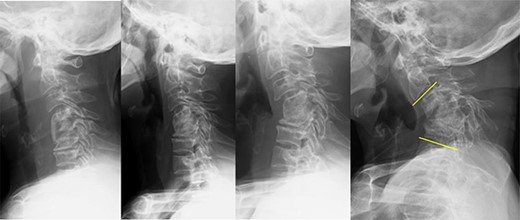

History of kyphosis after ACCF (anterior cervical corpectomy and fusion), and the patient had undergone ACCF 12 years ago for cervical spondylotic myelopathy; the kyphotic changes occurred early in the postoperative period and gradually progressed. POY1, 5, 12: Postoperative year 1, 5, 12.

A 69-year-old woman had undergone anterior cervical corpectomy and fusion 12 years ago for cervical spondylotic myelopathy. Postoperatively, her right-hand numbness and weakness had improved; however, her cervical alignment gradually became kyphotic because of bone graft collapse (Fig. 1). Ten years after surgery, she experienced severe neck pain, omalgia, mild numbness and muscle weakness in both upper limbs. Her symptoms deteriorated within 1 year, and she complained of horizontal gaze disturbances.